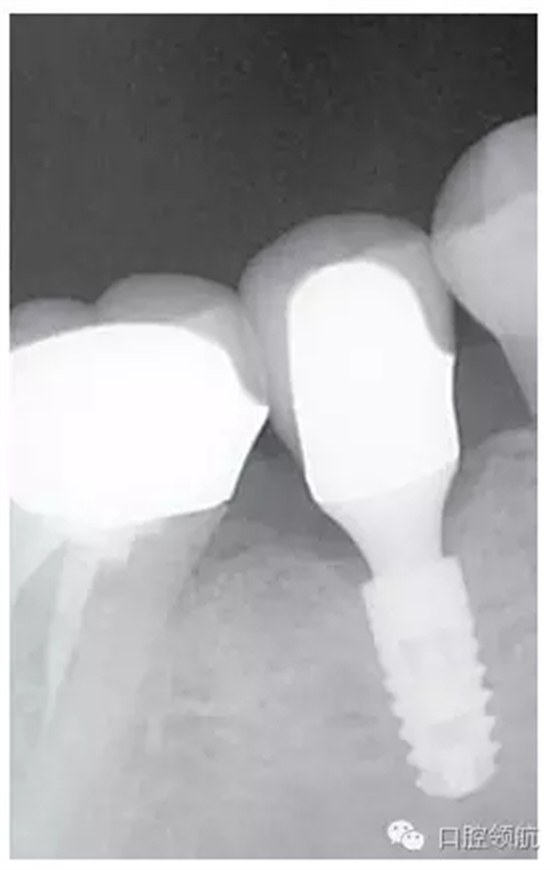

種植體的基臺(tái)與上部修復(fù)體的密合性,通過(guò)口腔X線片進(jìn)行檢查,確認(rèn)種植體周?chē)袣埩舻恼辰觿▓D2),使用探針等器械盡力清除剩余粘接劑,避免預(yù)后不良因素的產(chǎn)生。然后,通過(guò)X線片從投照的方向檢查確認(rèn)剩余的粘接劑,完全沒(méi)有殘留粘接劑的實(shí)際狀態(tài)(圖3)。

圖3 大約經(jīng)過(guò)3年的觀察未發(fā)現(xiàn)大的改變,與預(yù)期想象的一樣穩(wěn)定。